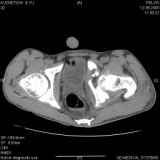

Уважаемые коллеги! Хотелось бы услышать совет по тактике лечения представлленого больного.Поступил после лечения в одном изотделений области. Травма 2,5 месяца назад. После выведенияиз шока был произведен остеосинтез перелома бедра, предплечья, до перевода к нам проводилосьвытяжение по оси шейки бедра за стержень, введенный в большой вертел. На сегодня деформацияригидна, клинически мобильности не определяется. Заранее признателен. P.S. Данный вид травм не включен в перечень "высокотехнологичных операций", направить длялечения по квотам Минздрава очень сложно.

Это обзорные и косые снимки

Привет, Леонид. Оскольчатый высокий двухколонный перелом в такие сроки трогать не надо, т.к. это про такие переломы сказано: "кто с ножом на Ж. пойдет тот в ней и останется...".